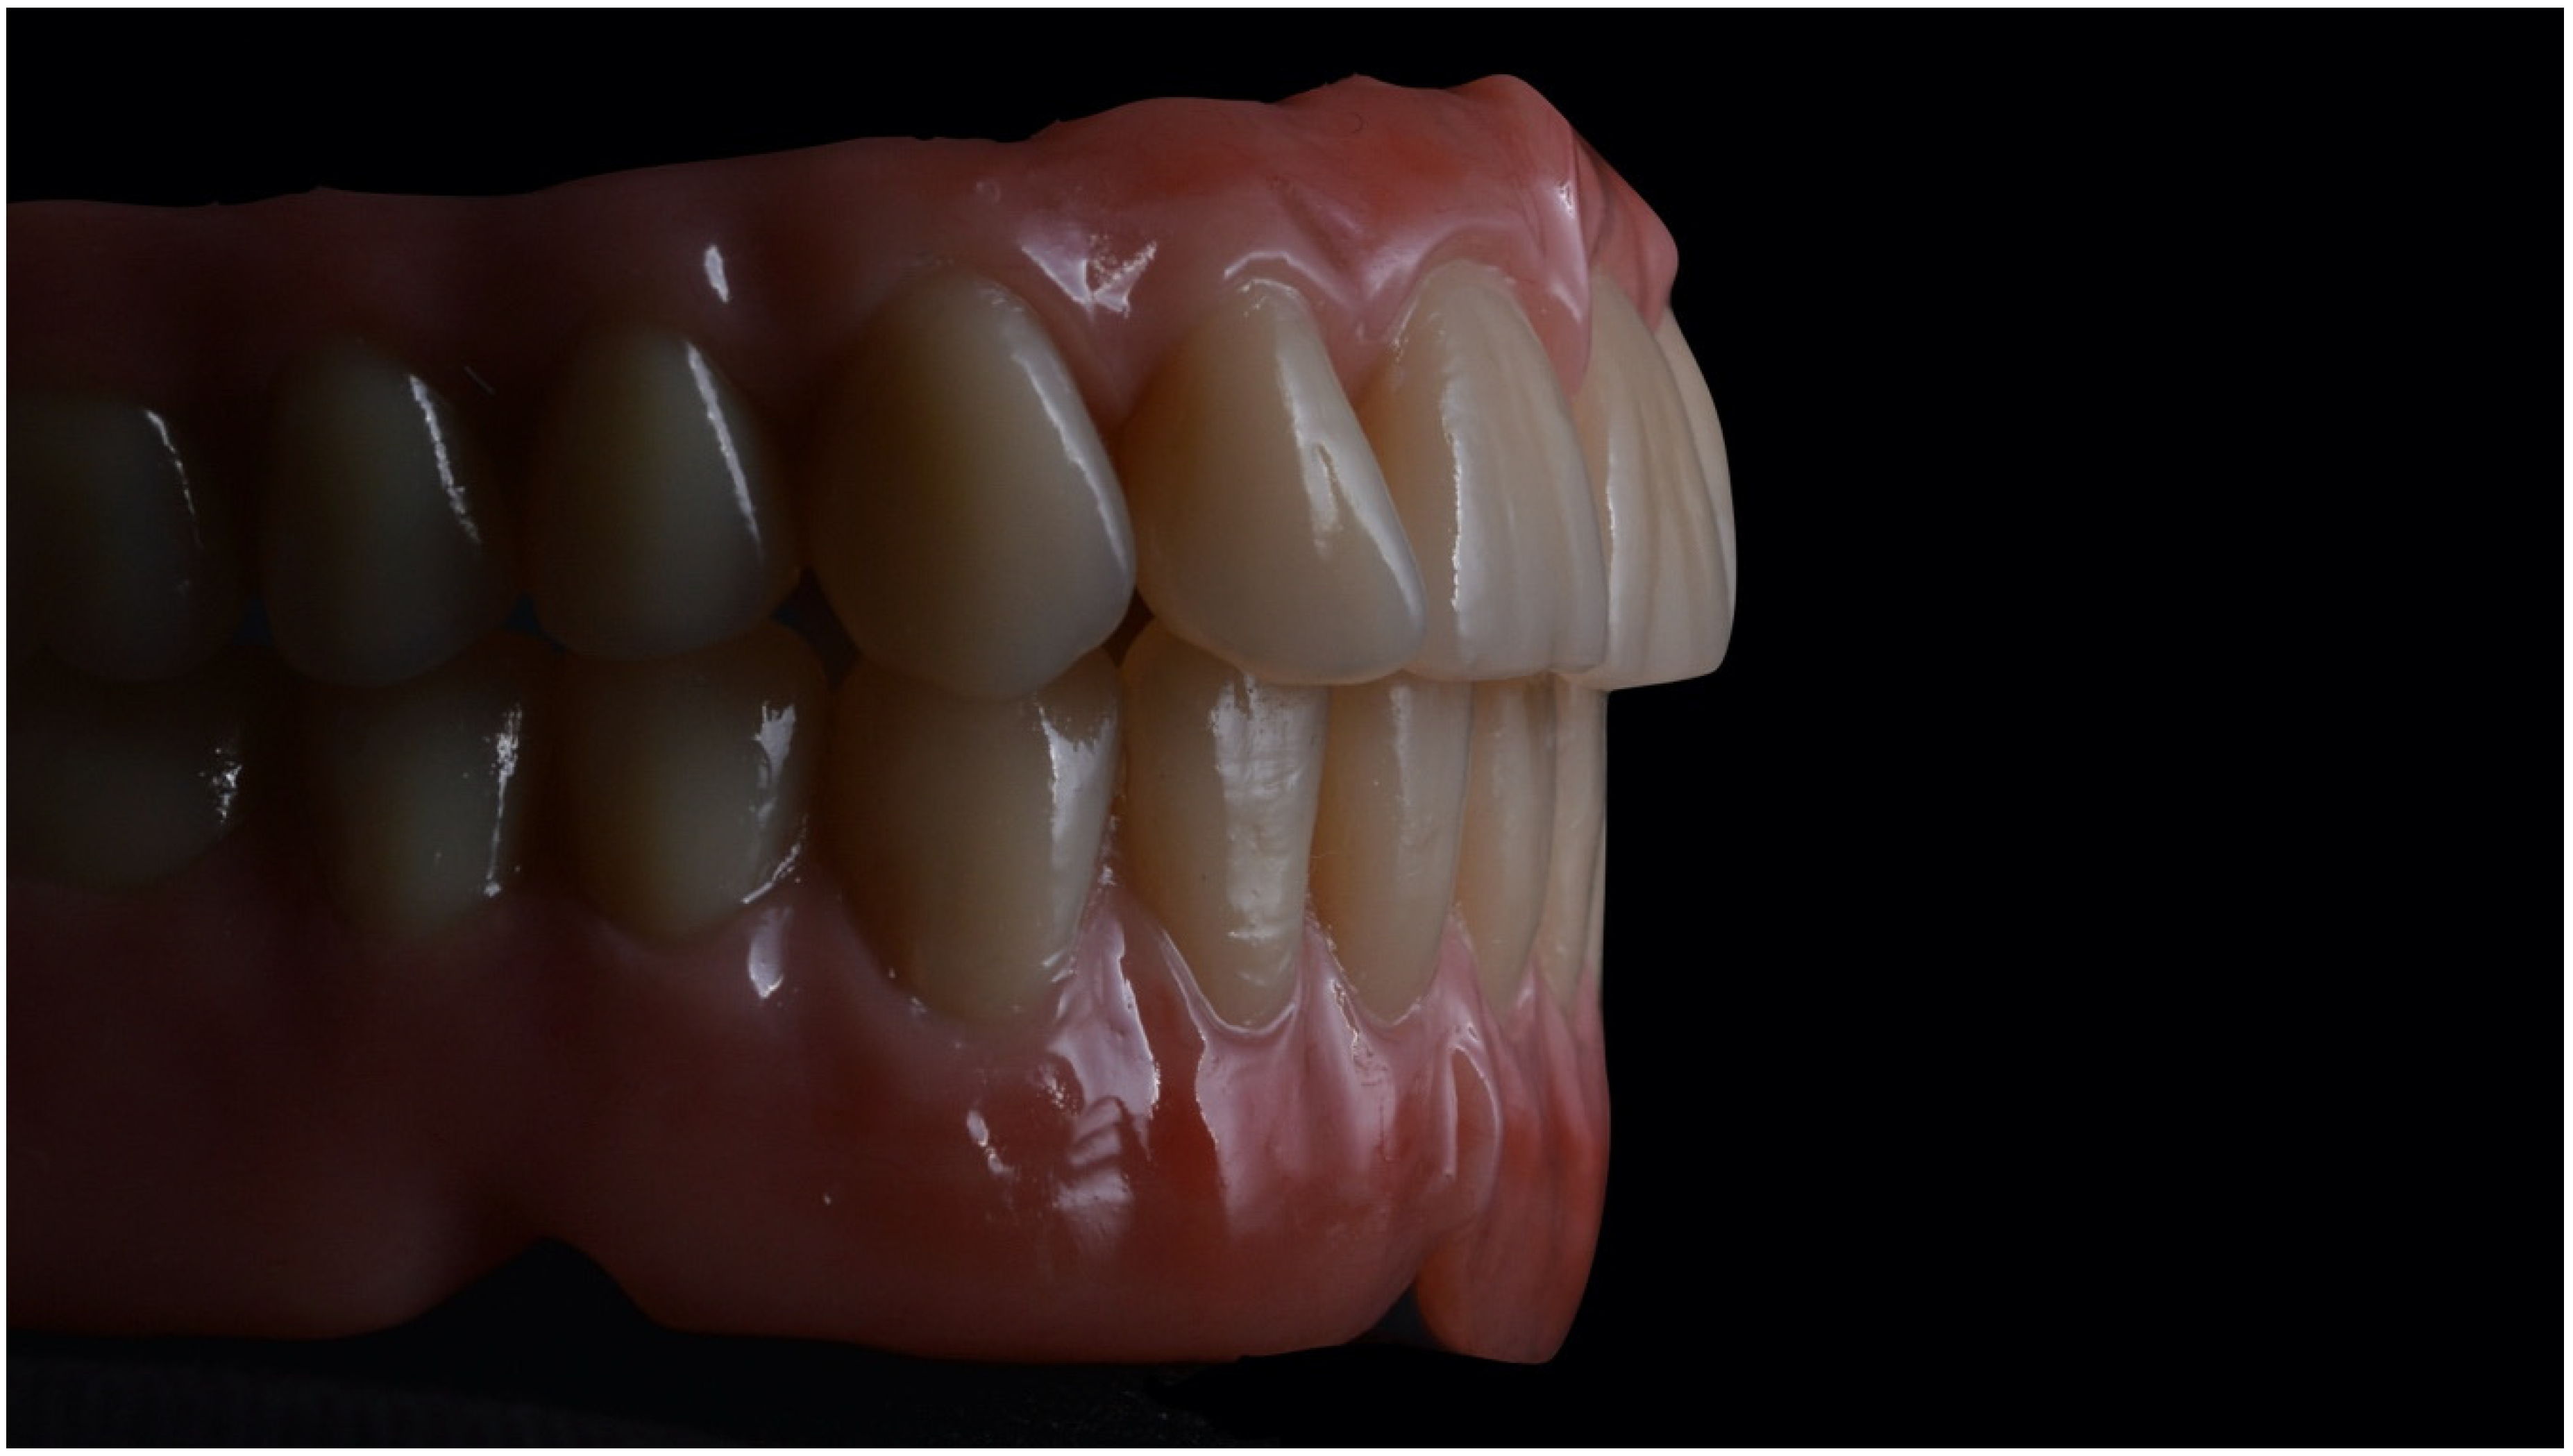

3. Results and Discussion